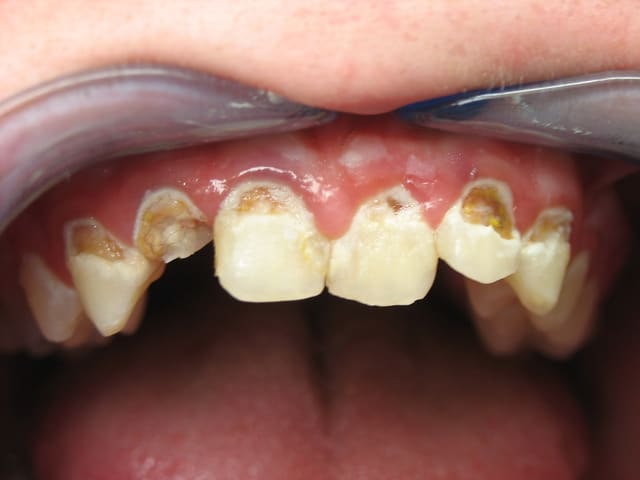

17 ans , un client pour le professeur de hontologie.

La honte c'est un peu aussi pour la célèbre boisson au goût acidulé.